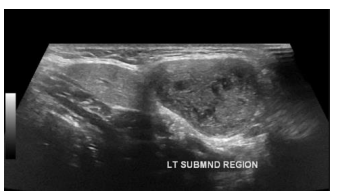

Você realiza o exame ultrassonográfico de glândulas salivares de uma paciente do sexo feminino de 30 anos e encontra a seguinte imagem. Assinale a alternativa correta.

Enunciado 4614330-1